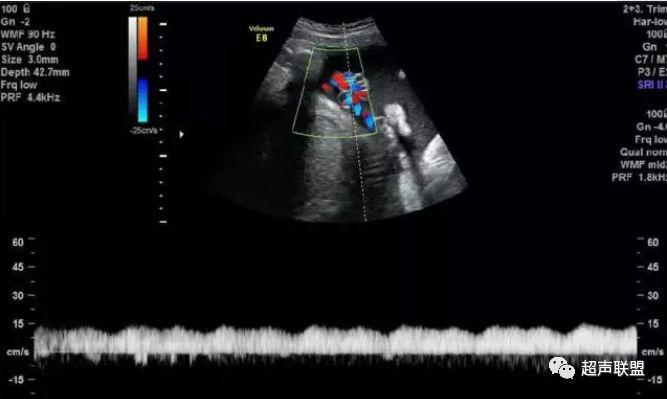

4 脐静脉频谱

胎儿宫内缺氧严重时脐静脉出现搏动。

6、脐静脉:脐静脉搏动(见于严重的胎儿宫内缺氧);

4、脐静脉搏动。

图9 脐静脉搏动